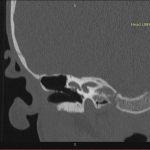

- Diagnosticul traumatismelor de bază de craniu

- Diagnosticul fracturilor:

- Complexe cranio-sinusale

- Complexe cranio-etmoidale

- Complexe cranio-orbitare

- Complexe cranio-faciale